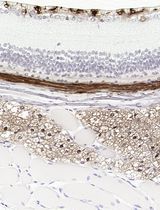

Improved Immunohistochemistry of Mouse Eye Sections Using Davidson's Fixative and Melanin Bleaching

AL Anne Nathalie Longakit

CH Chloe Hess

CZ Christina Zhang

CV Catherine D. Van Raamsdonk

1625 Views

Nov 20, 2025

Immunohistochemistry (IHC) and immunofluorescence (IF) are fundamental molecular biology techniques to assess protein expression. However, the melanin present normally in the eye in the uveal tract (choroid, iris, and ciliary body) and the retinal pigment epithelium (RPE) poses a significant challenge for IHC and IF. This is because melanin interferes with both chromogenic and fluorescent detection methods. Additionally, formalin fixation, which is commonly used for IHC, can result in shrinkage and loss of cellular detail in the eye. This protocol provides an optimized approach using Davidson’s fixative with a hydrogen peroxide bleaching step to eliminate melanin interference in the mouse eye, improving the quality and interpretability of IHC analyses of the uveal tract and RPE. It is particularly useful for the analysis of uveal melanoma.